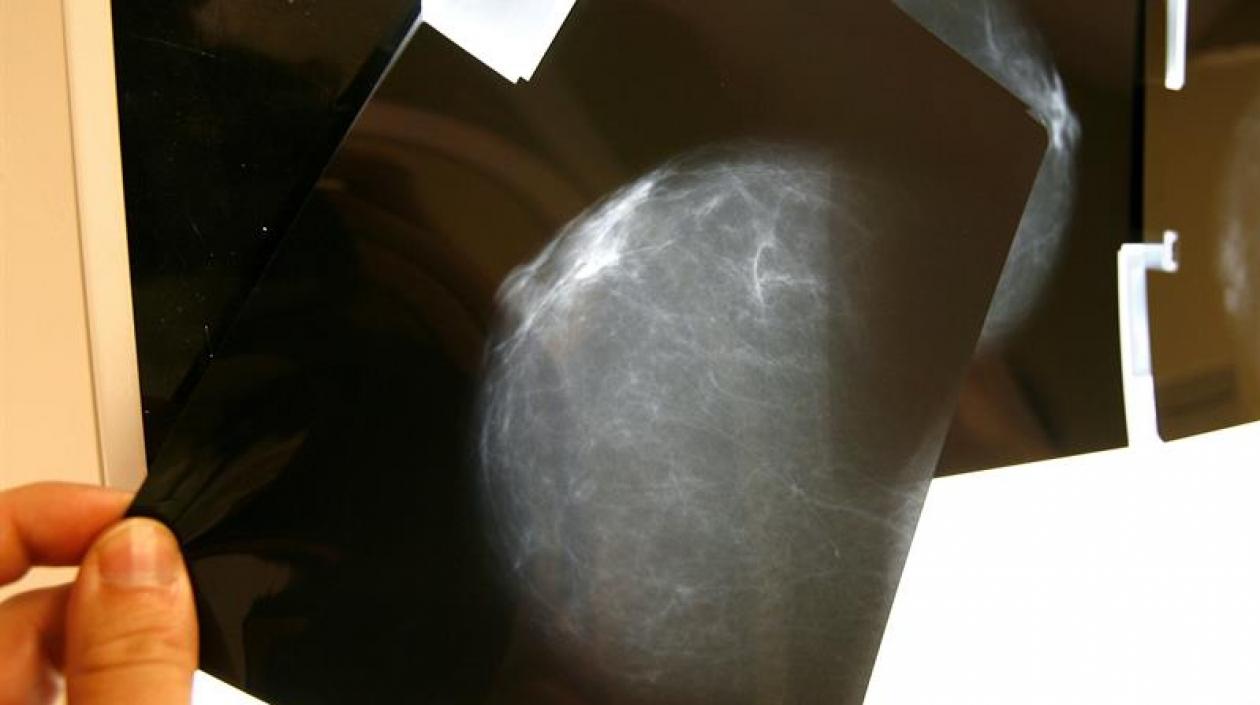

Detectado a tiempo el cáncer de seno es curable hasta en un 98 % de los casos.

Sin embargo, detectado a tiempo el cáncer de seno es curable hasta en un 98 % de los casos.